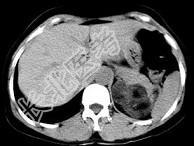

- 单项选择题男性,28岁, 左腰背酸胀5个月,CT检查如图所示, 应诊断为 ( )

A、左肾上腺髓样脂肪瘤

B、左肾上腺错构瘤

C、左肾上腺嗜铬细胞瘤

D、左肾上腺腺瘤

E、左肾上腺转移瘤